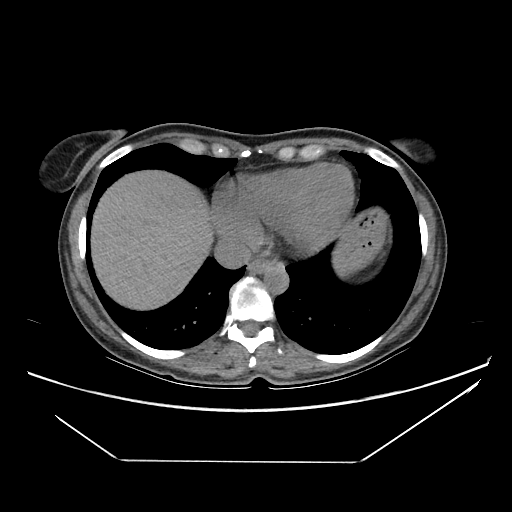

Image Grid

4Γ—3 grid: Rows show different image types (Original NATIVE, Reconstructed NATIVE, Original VENOUS, Generated VENOUS), Columns show windowing techniques (No Window, Lung Window, Mediastinum Window)

Generated VENOUS CT scan (A→B translation)

Full window (WL 1023.5, WW 4095 β†’ Low βˆ’1024, High +3071)